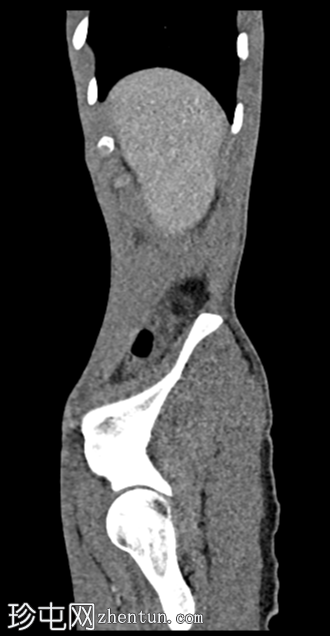

矢状位增强CT(门静脉期)

增强CT扫描显示双侧肾积水、输尿管积水伴输尿管黏膜弥漫性强化,以及膀胱容量缩小伴黏膜强化。未见尿路结石或肾周脂肪浸润/积聚。

考虑到患者有氯胺酮滥用史,CT扫描结果符合氯胺酮诱发性尿路病变的诊断。